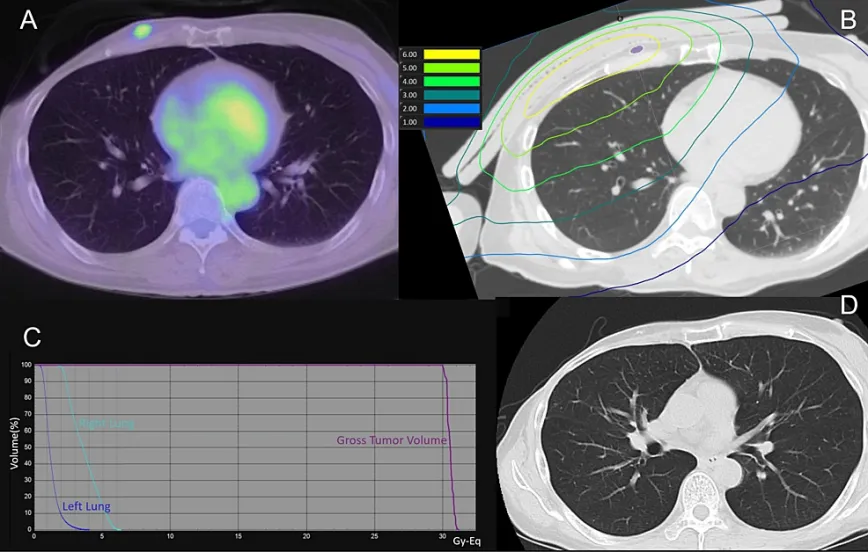

該患者因右側(cè)乳腺癌接受化療,隨后行保乳手術(shù),并在10年間進(jìn)行了25次總劑量為50Gy的保乳放療。3年前,患者因局部復(fù)發(fā)進(jìn)行了手術(shù)和化療,盡管先后進(jìn)行了兩次手術(shù)干預(yù)和激素治療,癌癥還是再次復(fù)發(fā),最終開始了BNCT治療。處方劑量最低為30Gy-Eq,同側(cè)肺平均劑量為3.7Gy-Eq。BNCT后第1、7、30、60和90天的CT掃描結(jié)果均未顯示放射性肺炎的證據(jù)。圖3為患者治療90天后的肺部劑量分布和CT掃描結(jié)果。

圖3

(A)治療前PET-CT。

(B) BNCT(肺)劑量分布圖。紫色表示腫瘤總體積

(C)劑量-體積直方圖

(D)治療后90天的CT掃描顯示腫瘤總體積縮小